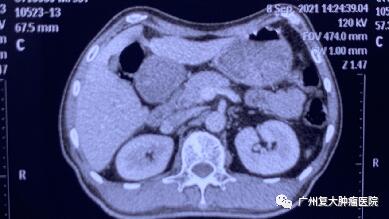

术后一周检查发现,身体各项指标逐步恢复正常。与之前相比,上腹部MRI图像提示胰腺、肝脏肿瘤中心大部分坏死。术后一年复查显示,肿瘤缩小,得到较好的控制。

▲术后一周

▲术后一年